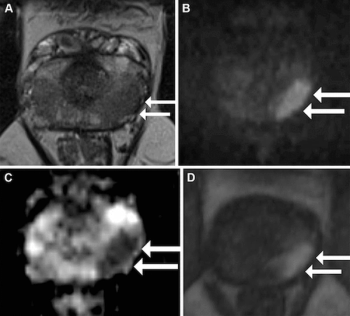

A model that combines MRI-based deep learning radiomics and clinical factors demonstrated an 84.8 percent ROC AUC and a 92.6 percent precision-recall AUC for predicting perineural invasion in prostate cancer cases.